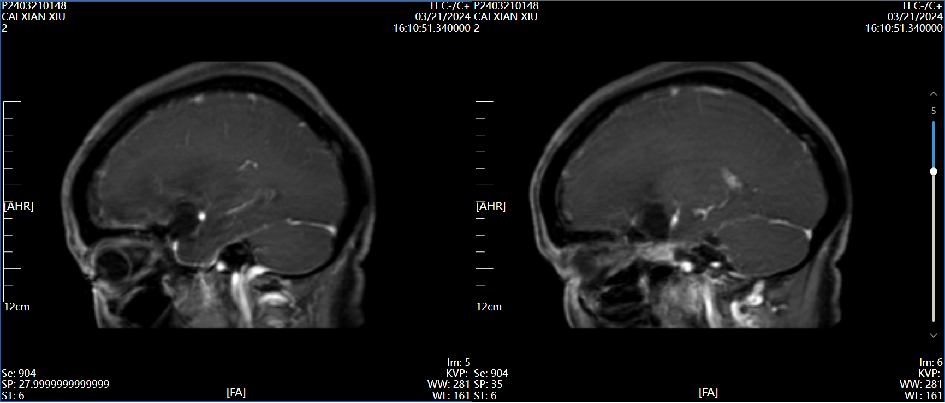

4、辅助检查:头颅磁共振检查提示:左侧前床突占位,约2.8×2.4×2.0cm大小,T1呈等低信号,T2呈等高信号,增强病灶明显强化,宽基底与前颅窝底、前床突相连,看见脑膜尾征。

术后第3天磁共振增强  2024.03.21